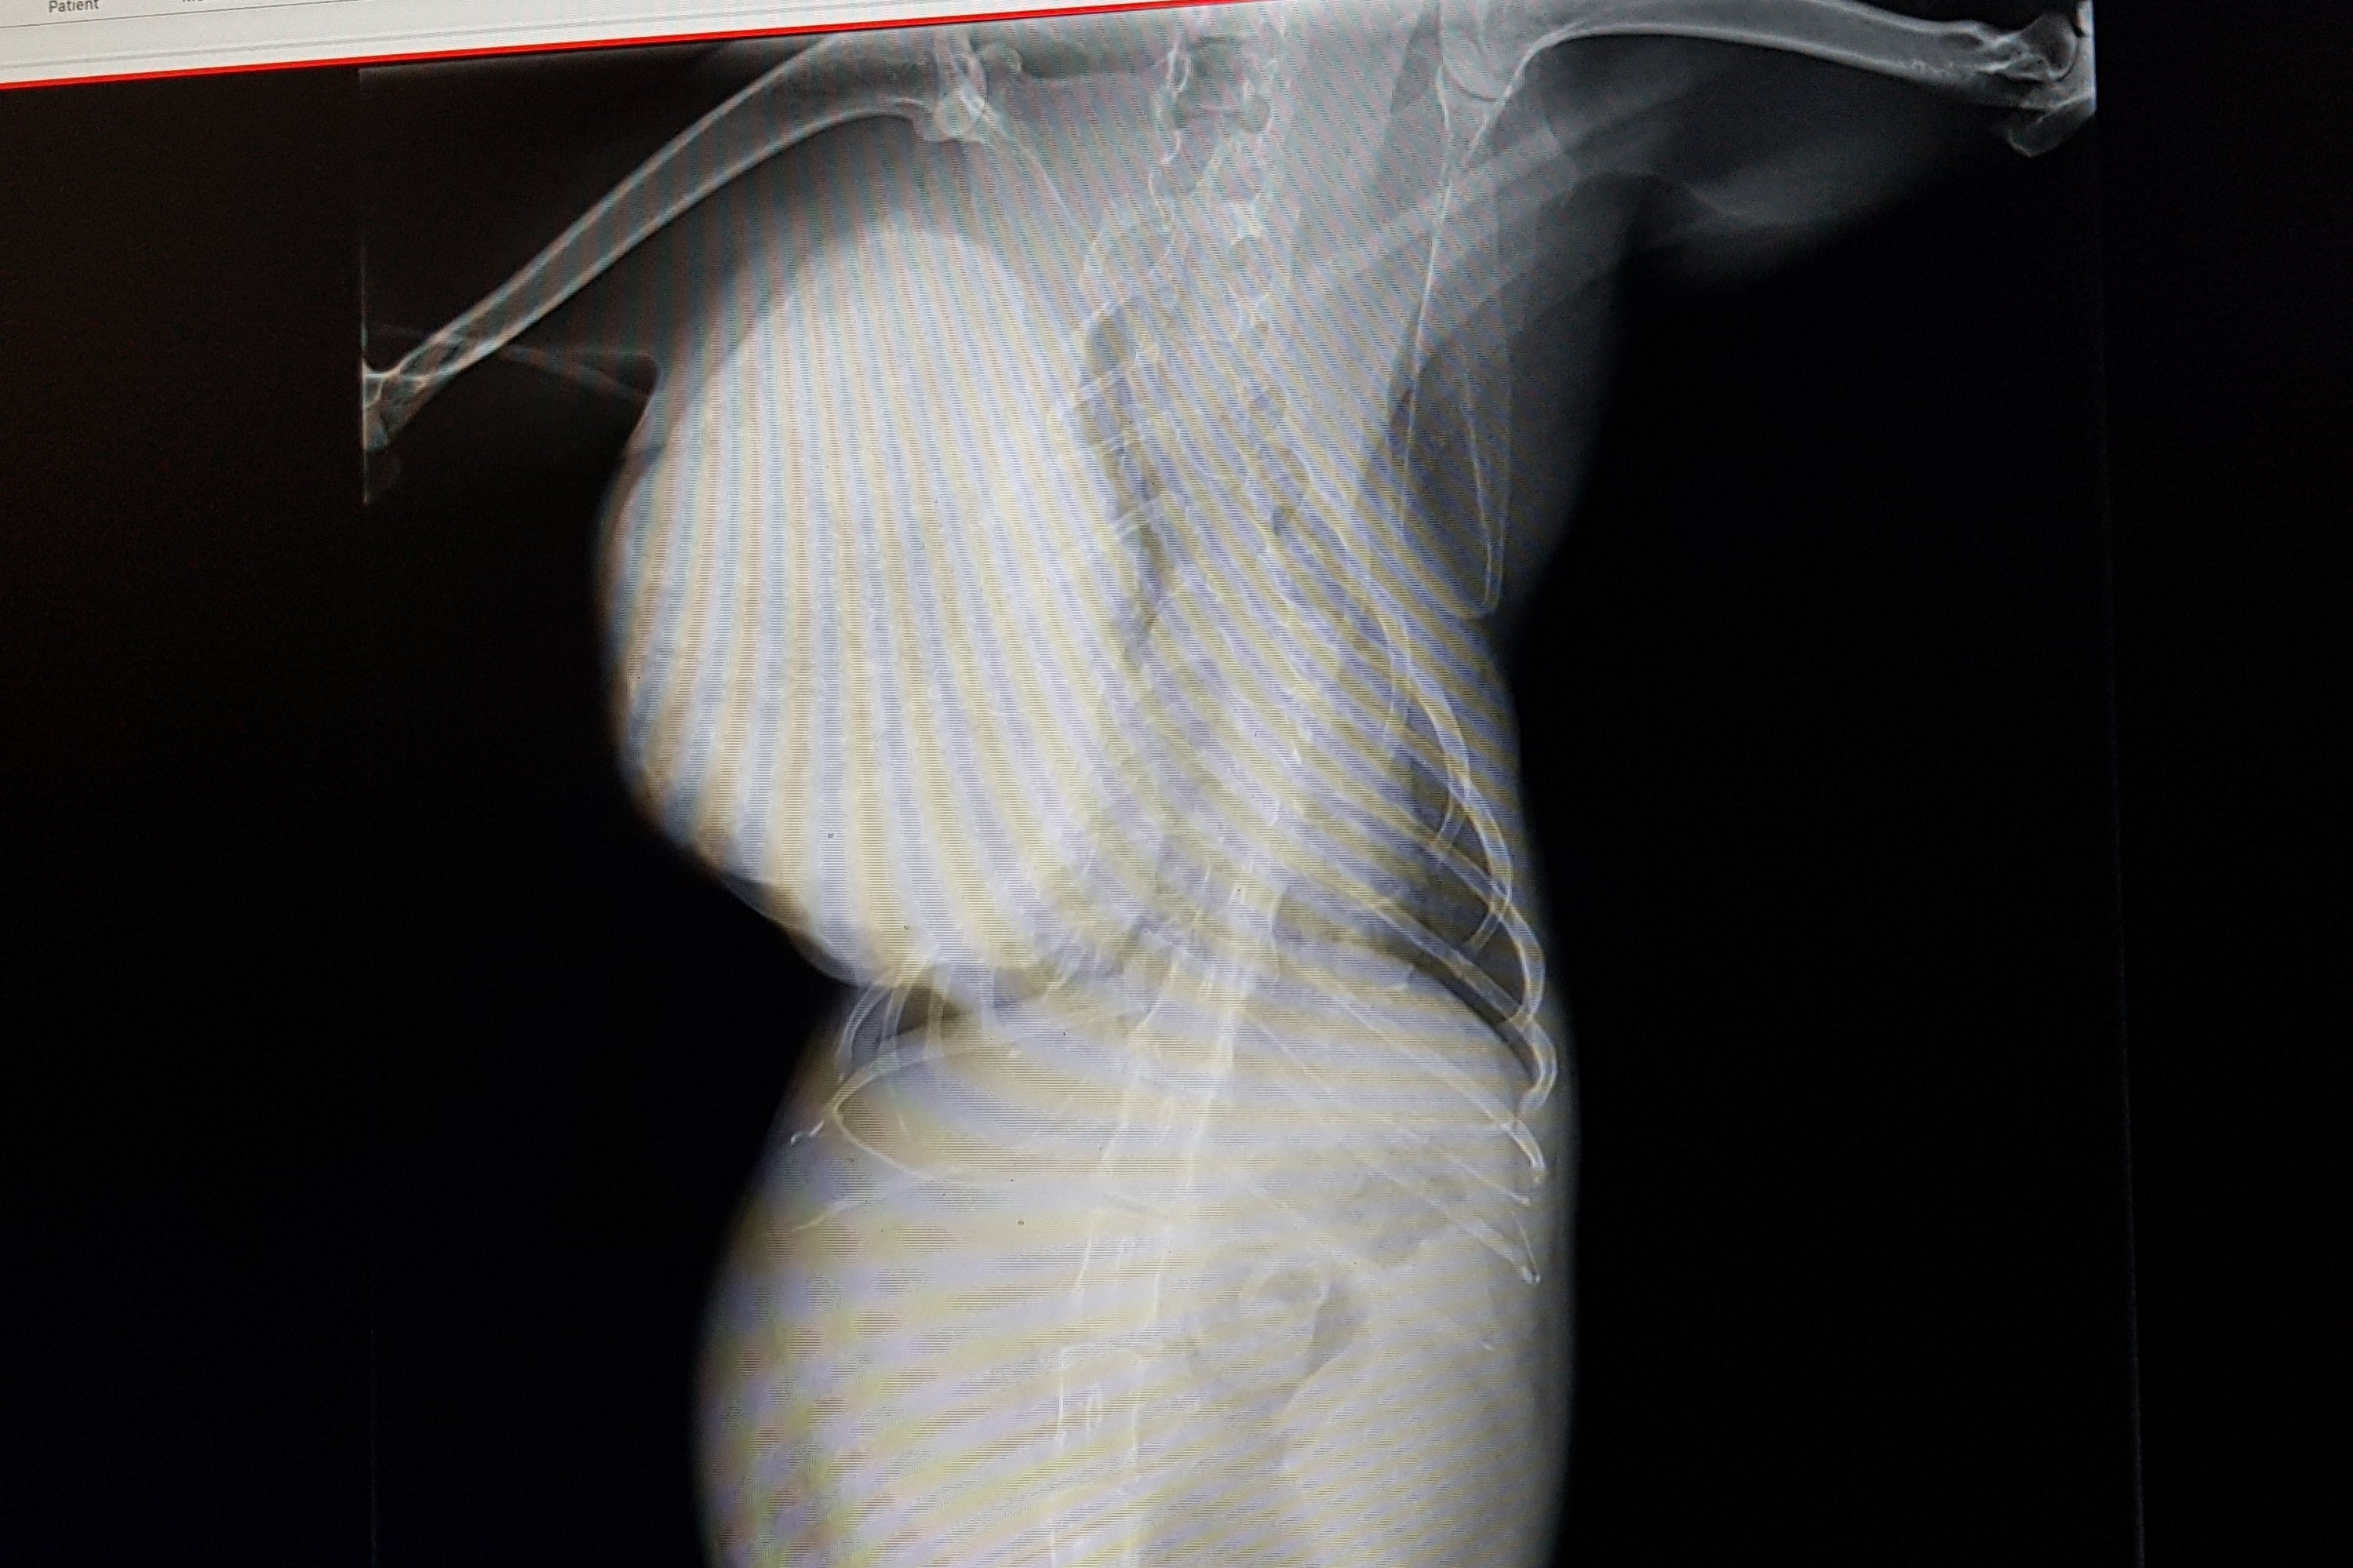

手術が出来るのかどうか中を開いてからしかわからず、手術をしても急変してしまう可能性もありましたが

これ以上腫瘍が大きくなると、皮膚が足りず閉じることが出来なくなるため

クラウドファンディングを待つ余裕がなく、すぐにでも手術をしなければなりませんでした。